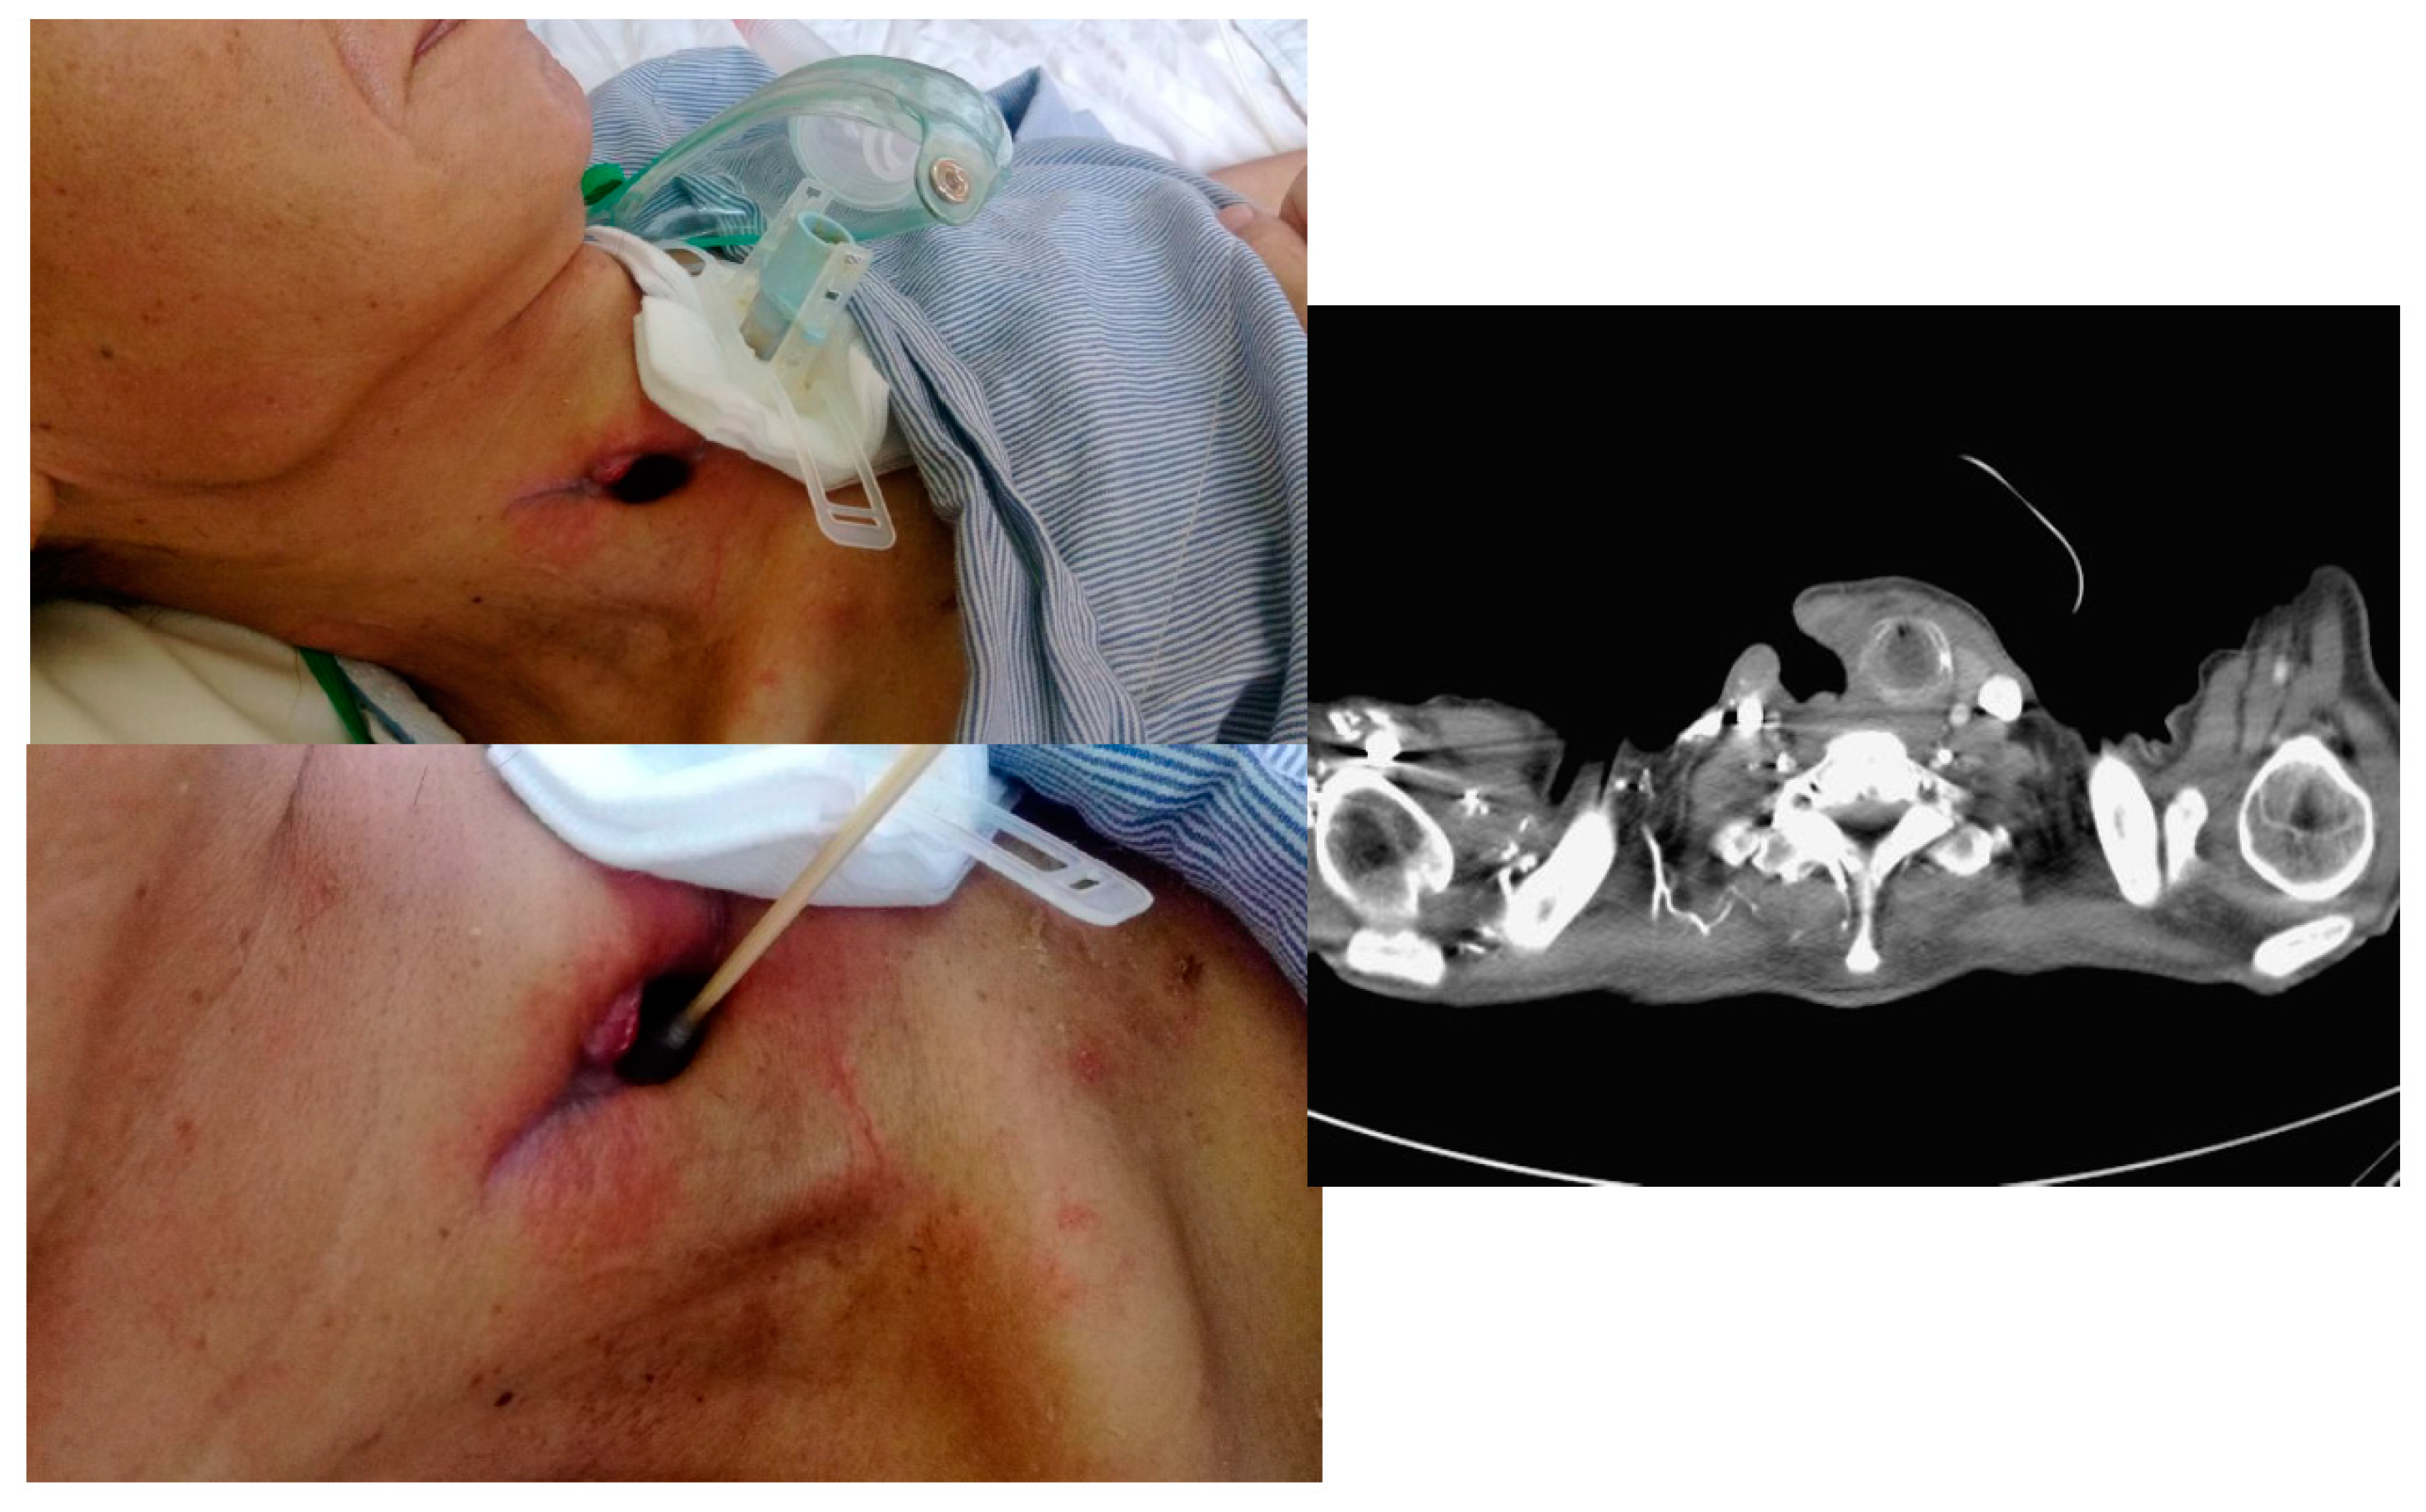

2. Case Presentation

2.1. Case 1

2.2. Case 2